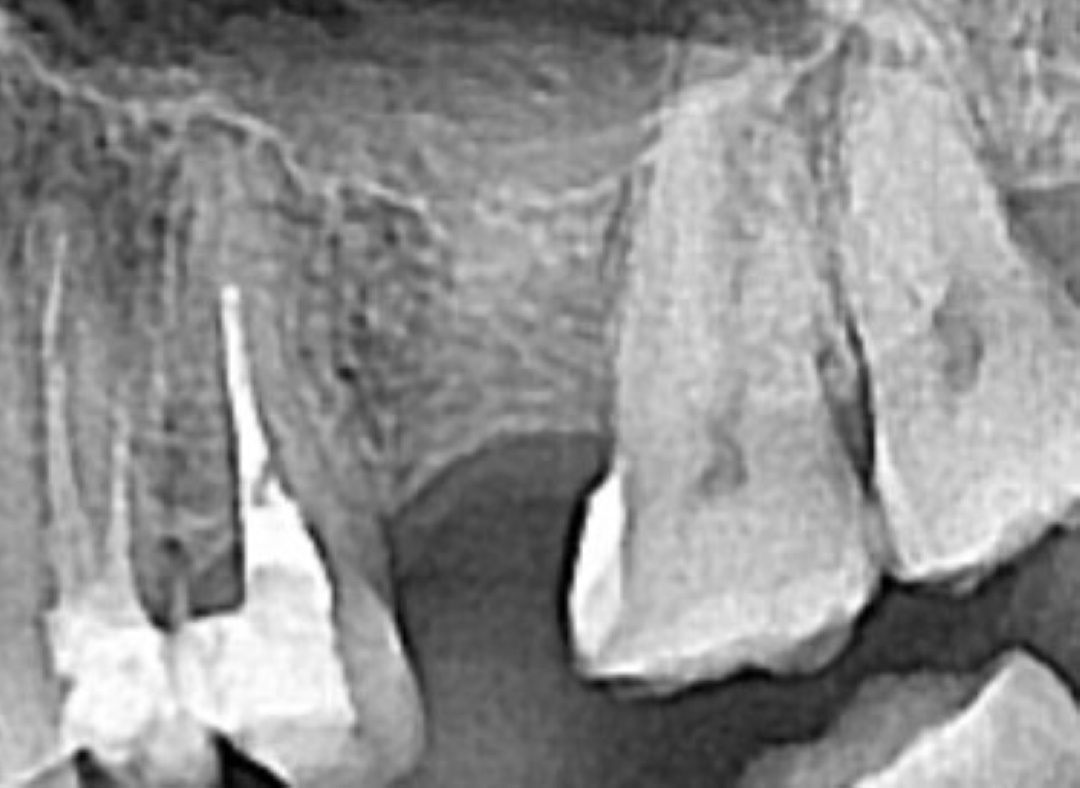

Клинический случай...

Отсутствие зуба 25

в течение очень длительного времени.

Смещение зуба 26 вперёд - дефицит места.

От ортодонтического лечение отказались.

Этап первый

Установлены ортодонтические винты в область бугра верхней челюсти слева, дана ортодонтическая тяга.

Этап второй

Через 3 месяца мы получили необходимое расстояние и установили имплантант Strauman Blt.

Этап третий

Ещё через 3 месяца мы убедились что имплант полностью интегрирован - пациент передан ортопеду на финальный этап - установку циркониевой коронки и реабилитацию эстетической зоны улыбки.

Доктора:

Ортодонт: Мосунова Ирина Вадимовна.

Хирург-имплантолог: Летягин Тарас Андреевич.